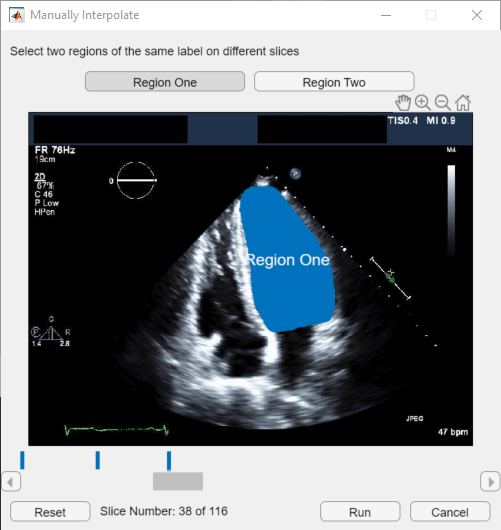

You can move through the image series and draw labels frame-by-frame, but the Medical Image Labeler app also provides interpolation tools in the Draw tab that can help you label an object between frames. Interpolation is most suitable between frames where the region of interest has a similar shape and size. In an echocardiogram, the ventricle experiences cycles of contraction, during which the ventricle rapidly changes in shape, and relaxation, during which the ventricle is relatively still. Therefore, you can most effectively use interpolation between the start and end of a relaxation period, such as between frames 20 and 38.

To use interpolation, you must first manually label a region in two frames. Label the ventricle in frame 20 and frame 38. If the Auto Interpolate button is not active, make sure the labeled region is selected by clicking Select Drawn Region in the app toolstrip and selecting the labeled region.

Click Auto Interpolate. The app automatically labels the ventricle in the intermediate frames. The app adds bars above the slider to indicate all the frames that have labeled pixels, which now appears as a solid bar from frame 20 to frame 38.

Alternatively, after labeling an ROI on two frames, you can click Manually Interpolate. With this option, the app opens the Manually Interpolate dialog box. Select the two regions between which you want to interpolate, Region One and Region Two. To select the first region, use the slider at the bottom of the dialog box to navigate to frame 20, and then click inside the labeled ventricle. To select the second region, click Region Two, navigate to frame 38, and click inside the labeled ventricle. After selecting both regions, click Run to interpolate the label in the intermediate frames.